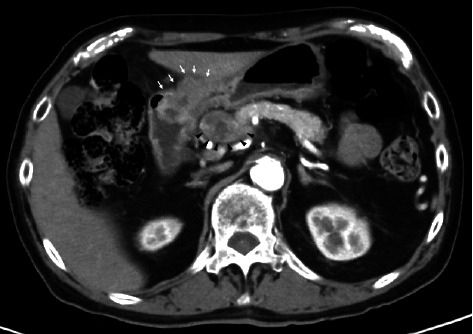

背景:人表皮生长因子受体2 (HER2)阳性胃癌约占胃癌病例的15%。曲妥珠单抗(Trz)是一种靶向HER2的单克隆抗体,已被证明与化疗联合可提高总生存率。然而,虽然trz诱导的心脏毒性(TIC)是乳腺癌化疗中公认的不良反应,但关于其在胃癌治疗中的发生的报道仍然有限。病例介绍:一名80岁日本男性her2阳性晚期胃癌(ciii期)患者在术后使用Trz + SOX方案(Trz、奥沙利铂和TS-1)化疗时出现室性心律失常和心力衰竭。患者最初因贫血和幽门狭窄行远端胃切除术并D1+淋巴结切除术。转移到#8a淋巴结(肝总动脉前上淋巴结)和通过淋巴结侵入胰腺的患者采用两个周期的Trz + SOX方案治疗,导致部分缓解。然而,在第11个周期后,他出现室性心动过速和心力衰竭。心脏影像学和实验室检查未发现冠状动脉病变或结构异常,提示TIC是根本原因。药物抗心律失常治疗导致症状缓解,无心律失常或心力衰竭复发。讨论:本病例强调了以非蒽环类药物为基础的Trz治疗胃癌的潜在心脏毒性。病理生理学上,HER2信号抑制可能会损害心肌细胞的应激反应和修复机制。患者的高龄、高血压和贫血史以及长期接受化疗可能是心脏易感性增加的原因。仔细监测心功能对于接受trz为基础的胃癌治疗的老年和合并症患者至关重要,以减轻心脏毒性的风险。结论:以trz为基础的化疗治疗her2阳性胃癌,即使不使用蒽环类药物,也可能造成心脏毒性的风险,特别是在老年人或合并症患者中。需要进一步的研究来阐明潜在的机制,优化这一人群的监测和预防策略。

Background: Human epidermal growth factor receptor 2 (HER2)-positive gastric cancer accounts for approximately 15% of gastric cancer cases. Trastuzumab (Trz), a monoclonal antibody targeting HER2, has been shown to improve overall survival when combined with chemotherapy. However, while Trz-induced cardiotoxicity (TIC) is a well-recognized adverse effect in breast cancer chemotherapy, reports on its occurrence in gastric cancer treatment remain limited. Case Presentation: An 80-year-old Japanese male with HER2-positive advanced gastric cancer (cStage III) developed ventricular arrhythmia and heart failure during postoperative chemotherapy with the Trz + SOX regimen (Trz, oxaliplatin, and TS-1). The patient initially underwent distal gastrectomy with D1+ lymphadenectomy for anemia and pyloric stenosis. Metastasis to the #8a lymph node (anterior superior lymph node of the common hepatic artery) and pancreatic invasion via lymph nodes were treated with two cycles of the Trz + SOX regimen, leading to a partial response. However, after the 11th cycle, he developed ventricular tachycardia and heart failure. Cardiac imaging and laboratory findings revealed no coronary artery disease or structural abnormalities, suggesting TIC as the underlying cause. Antiarrhythmic therapy with pharmacological agents led to symptom resolution, and no recurrence of arrhythmia or heart failure was observed. Discussion: This case highlights the potential cardiotoxicity associated with nonanthracycline-based Trz regimens for gastric cancer. Pathophysiologically, HER2 signaling inhibition in cardiomyocytes may impair stress responses and repair mechanisms. The patient's advanced age, history of hypertension and anemia, and cumulative exposure to chemotherapy may have contributed to increased cardiac vulnerability. Careful monitoring of cardiac function is essential in elderly and comorbid patients undergoing Trz-based therapy for gastric cancer to mitigate the risk of cardiotoxicity. Conclusion: Trz-based chemotherapy for HER2-positive gastric cancer, even without anthracyclines, may pose a risk of cardiotoxicity, particularly in elderly or comorbid patients. Further research is warranted to elucidate underlying mechanisms and optimize monitoring and prevention strategies in this population.